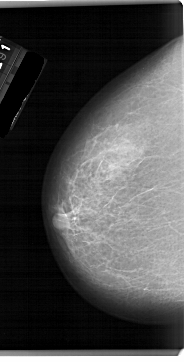

LEFT_MLO LINES 6871 PIXELS_PER_LINE 3526 BITS_PER_PIXEL 12 RESOLUTION 43.5 NON_OVERLAY